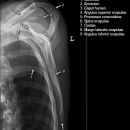

Schulter nach Morrison oder Outlet View

Indikation

v.a. Impingementsyndrom: Beurteilung des Akromions, des AC-Gelenks, evtl. hilfreich zur Diagnostik von Luxationen

Beurteilungskriterien

- Impingementsyndrom (2): Neigungswinkel des Akromions -> Je gebogener bzw. hakenförmiger desto höher ist die Wahrscheinlichkeit. Radiologische Befunde: Zystenbildung im Bereich des Tuberculum majus? Subchondrale Sklerosierung am Tuberculum majus oder subacromiale Osteophytenbildung? Verkalkungen im Verlauf der Supraspinatussehne?

- subacrominalen Raumes: normalerweise 1 - 1,5 cm, < 10 mm -> wahrscheinlich, < 6 mm -> sicher pathologisch